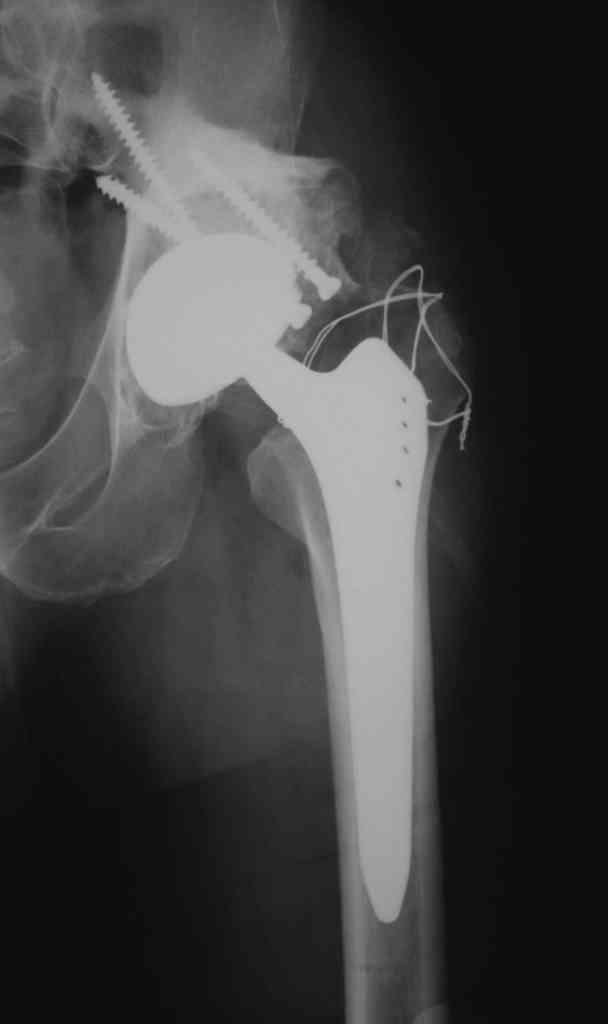

Еще одно наблюдение, неправильно сросшийся перелом заднего отдела ВВ с ввихом головки бедра 16-и летней давности.

С уважением, Р.Тихилов